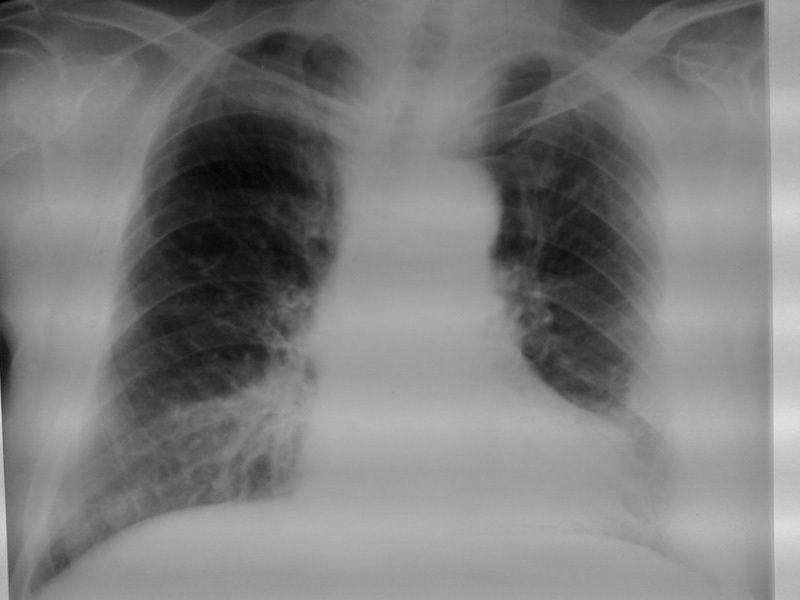

以下是引用李衡钧在2008-6-16 16:46:00的发言:[br]心尖较为陡直,首先考虑冠心病。进一步检查除外室壁瘤。[br]不太像包裹积液和心包囊肿。因为其边缘不是明显锐利清晰。

以下是引用zhangkai在2008-6-16 15:12:00的发言:[br]左下侧胸壁包裹性积液?[br]心脏改变建议结合透视、临床听诊、超声检查排除室壁瘤可能。